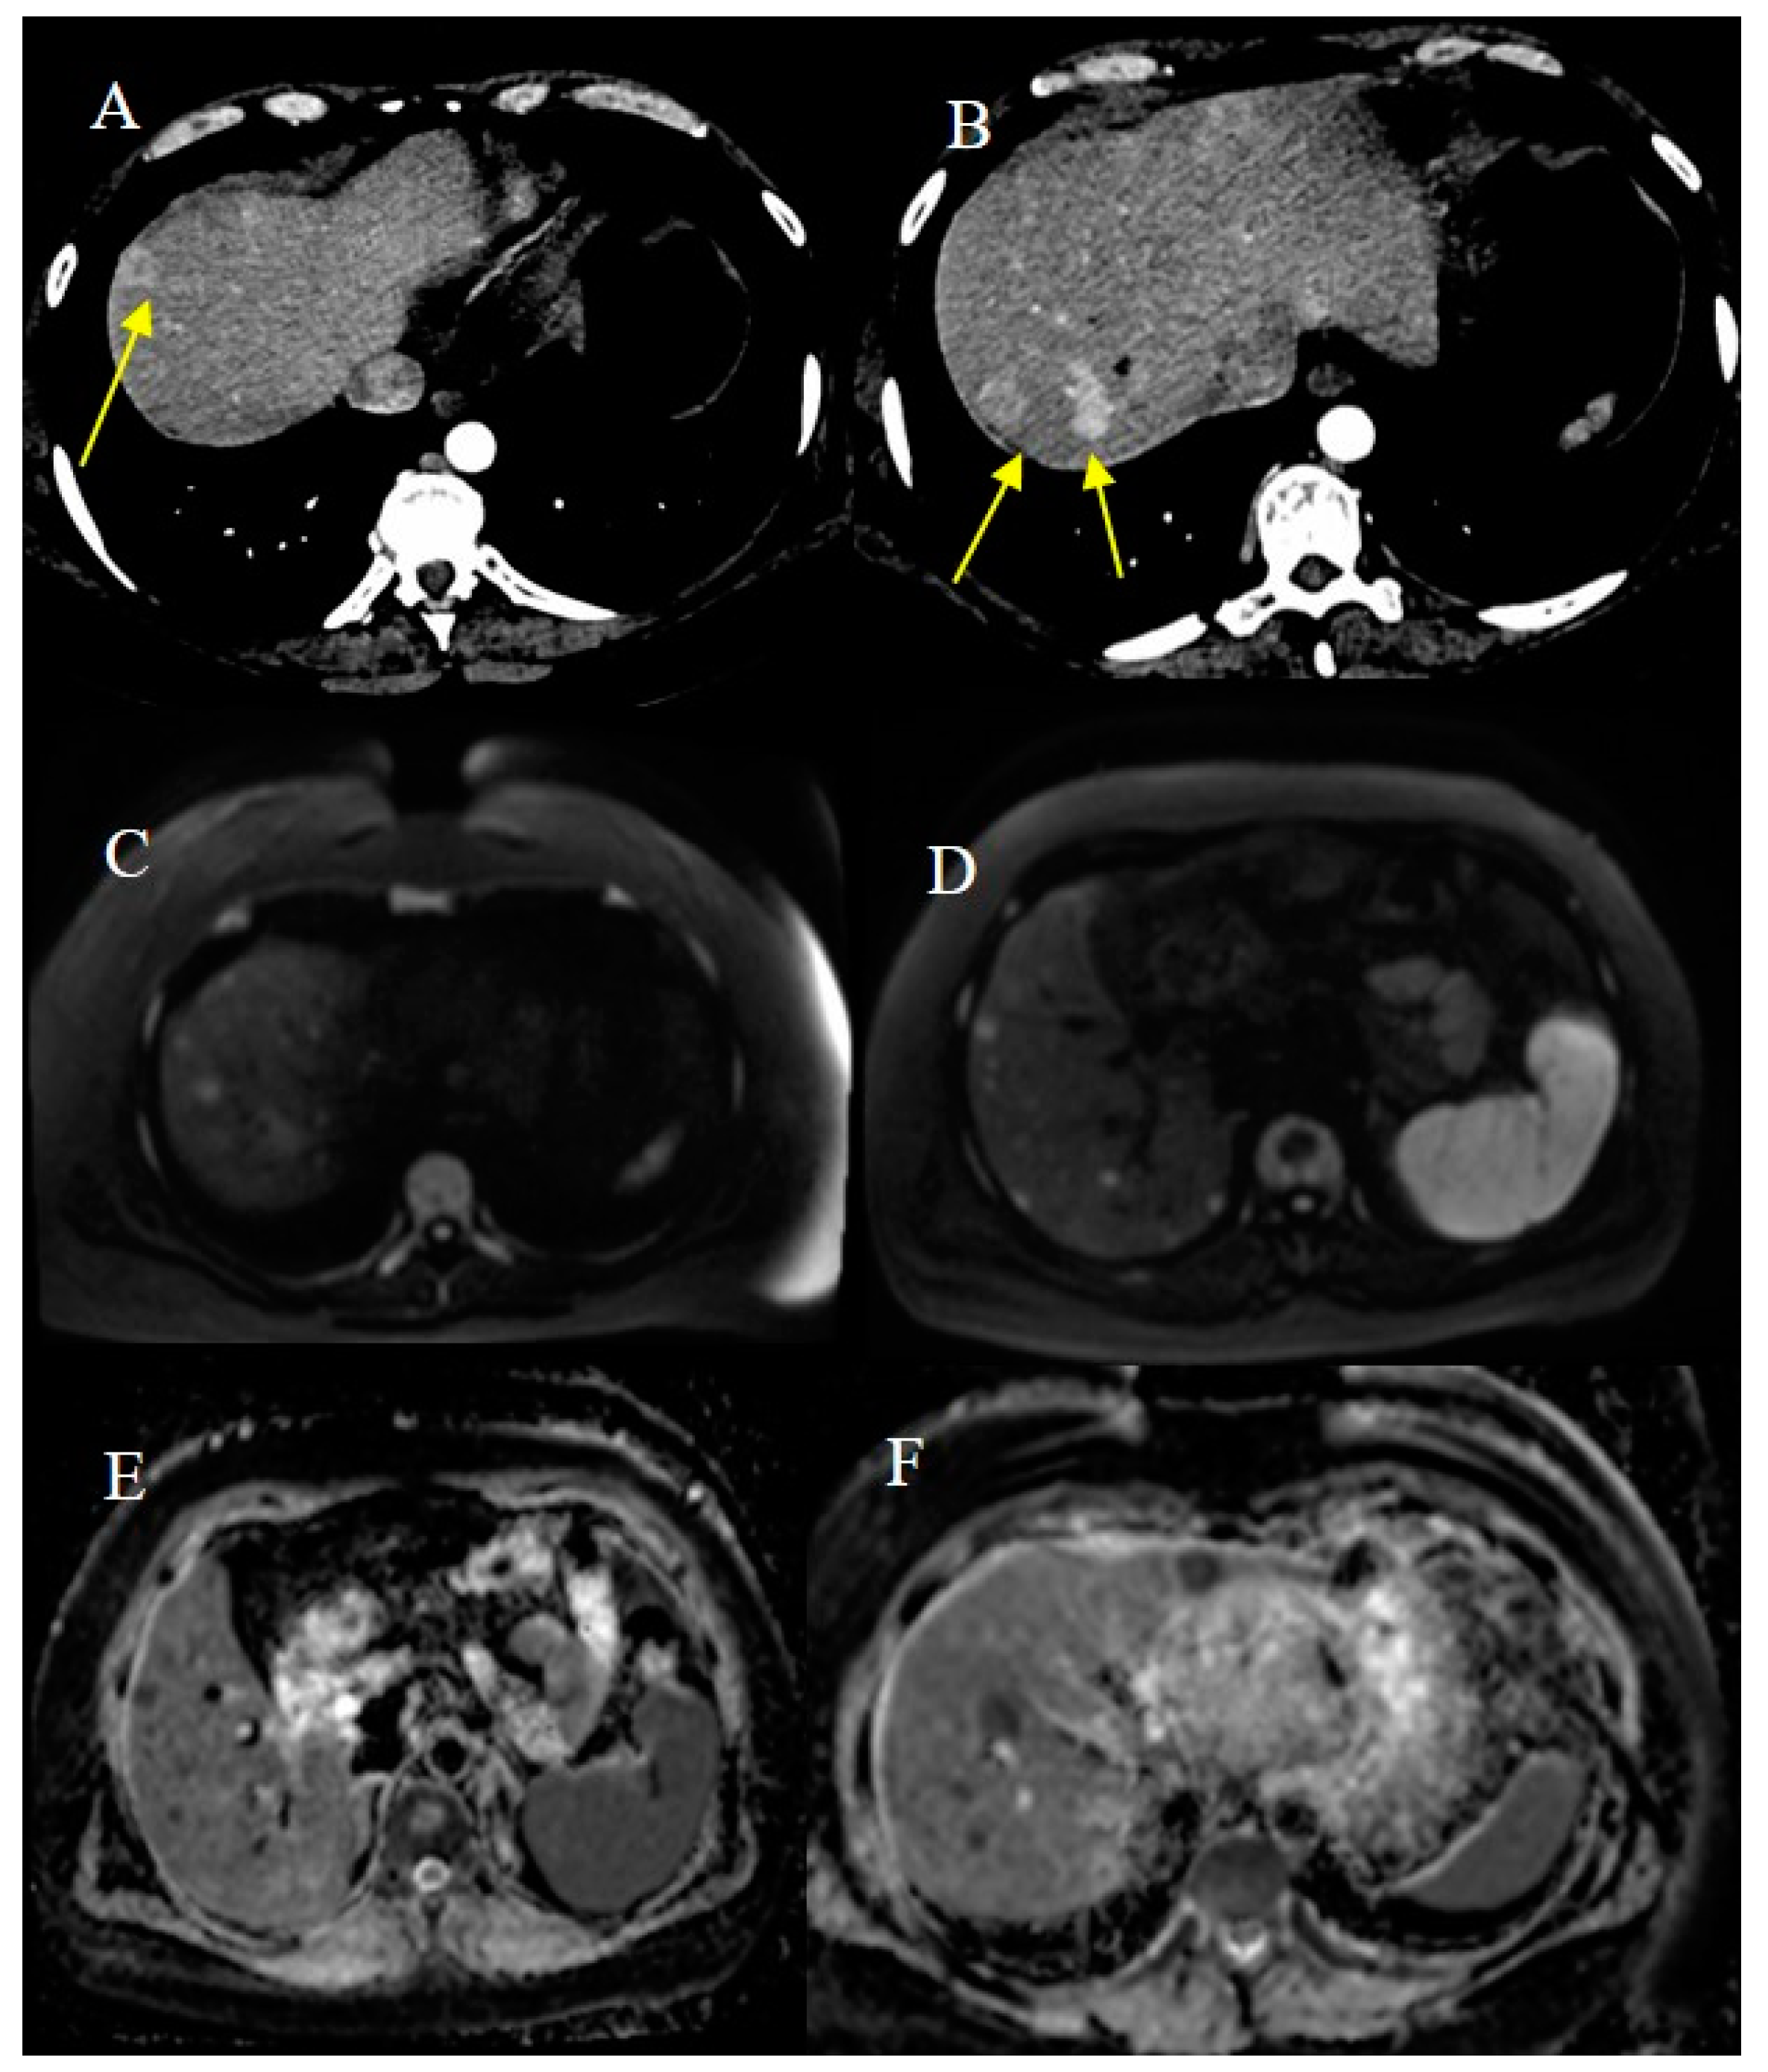

- Attiyeh, M.A.; Malhotra, G.K.; Li, D.; Manoukian, S.B.; Motarjem, P.M.; Singh, G. Defining MRI Superiority over CT for Colorectal and Neuroendocrine Liver Metastases. Cancers 2023, 15, 5109. [Google Scholar] [CrossRef]

- Shenoy-Bhangle, A.; Baliyan, V.; Kordbacheh, H.; Guimaraes, A.R.; Kambadakone, A. Diffusion weighted magnetic resonance imaging of liver: Principles, clinical applications and recent updates. World J. Hepatol. 2017, 9, 1081. [Google Scholar] [CrossRef]

- Masselli, G.; Casciani, E.; Polettini, E.; Laghi, F.; Gualdi, G. Magnetic resonance imaging of small bowel neoplasms. Cancer Imaging 2013, 13, 92–99. [Google Scholar] [CrossRef] [PubMed]

- Faggian, A.; Fracella, M.R.; D’alesio, G.; Alabiso, M.E.; Berritto, D.; Feragalli, B.; Miele, V.; Iasiello, F.; Grassi, R. Small-Bowel Neoplasms: Role of MRI Enteroclysis. Gastroenterol. Res. Pract. 2016, 2016, 9686815. [Google Scholar] [CrossRef]

- Maccioni, F.; Busato, L.; Valenti, A.; Cardaccio, S.; Longhi, A.; Catalano, C. Magnetic resonance imaging of the gastrointestinal tract: Current role, recent advancements and future prospectives. Diagnostics 2023, 13, 2410. [Google Scholar] [CrossRef] [PubMed]

- Lu, J.; Zhou, Z.; Morelli, J.N.; Yu, H.; Luo, Y.; Hu, X.; Li, Z.; Hu, D.; Shen, Y. A systematic review of technical parameters for MR of the small bowel in non-IBD conditions over the last ten years. Sci. Rep. 2019, 9, 14100. [Google Scholar] [CrossRef]